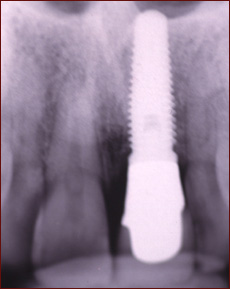

Dental implants are titanium posts that are patterned after the structure of your natural teeth. They are placed at the site of the missing teeth and offer function and esthetics nearly identical to the missing teeth.

Implant Is Patterned After The Natural Root and Tooth.

Implant is Placed into Space to Replace Root and Tooth.

*Images courtesy of 3i Implant Innovations